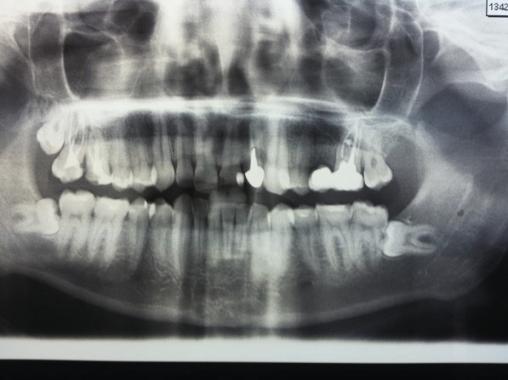

Louis, 20 ans, sans antécédent, se présente à sa visite médicale périodique. On découvre une protubérance gingivale inquiétante (photo 1 ) au niveau de la table osseuse externe de la dent n° 16. Fluctuante et régulière, elle ne saigne pas au contact.